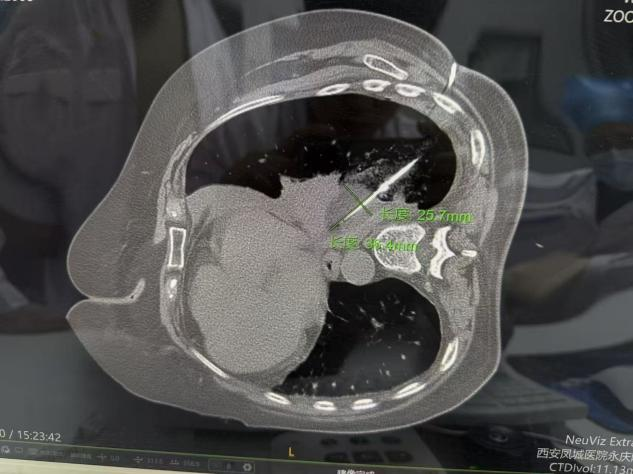

病例一

此次接受手术的两位患者,因身体基础状况、病灶位置等因素,均不适合传统外科手术治疗。胸外科开科后,第一时间组织团队对患者病情进行全面评估,联合医学影像科等科室开展MDT多学科讨论,为两位患者量身定制了个体化冷冻消融治疗方案。手术在局部麻醉下进行,在CT实时精准引导下,将超细冷冻消融针穿刺至病灶核心区域,通过超低温冷冻,精准摧毁病变细胞,同时最大程度保护周边正常组织和重要血管、神经。整个手术过程高效、微创,两位患者术中生命体征平稳,全程保持清醒且痛感轻微,皮肤上仅留针眼大小的创口。术后即刻复查影像显示,消融范围覆盖病灶,达到预期治疗效果。术后患者恢复迅速,2小时内即可下床活动,有效缩短了住院周期,患者及家属对治疗效果和就医体验均表示高度认可并送来锦旗感谢。